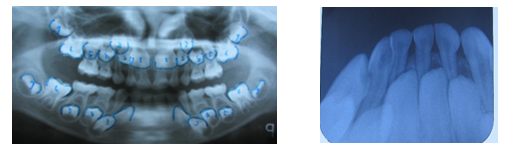

① 上下顎前歯部反対咬合

② 上顎右上中切歯が、斜めに生えている。

③ 下顎前歯が、重なっている。(叢生)

智歯と下顎前歯部不明箇所以外の永久歯は全て存在しています。

(模型所見)

歯の大きさ(歯幅mm)